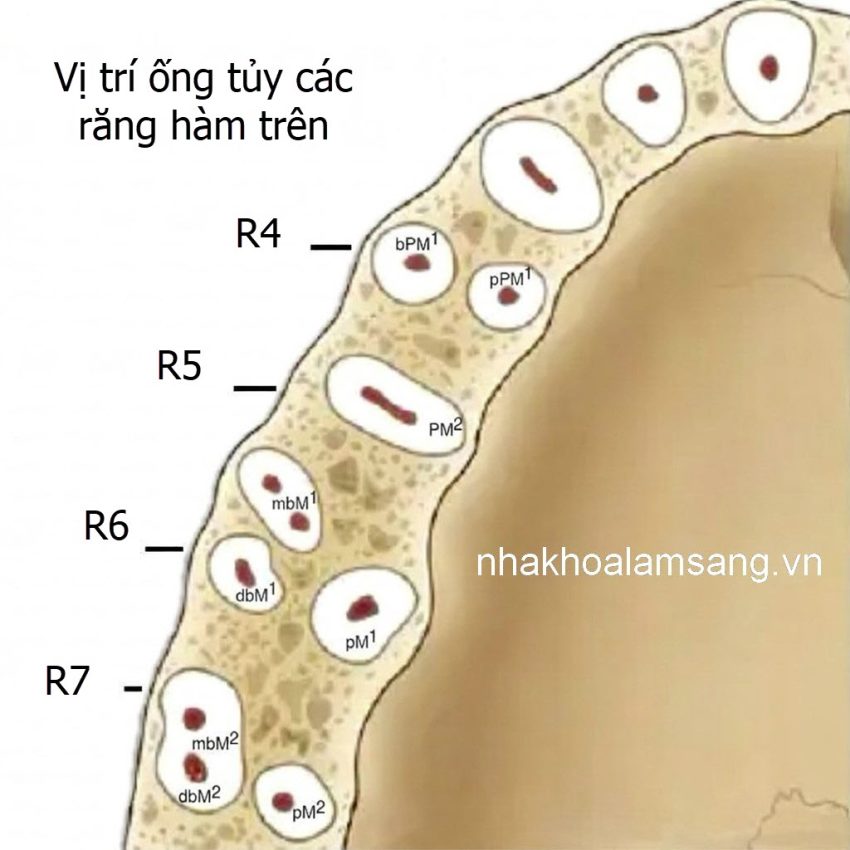

Trong nội nha việc xác định đúng vị trí các ống tủy răng hàm trên là bước then chốt quyết định trực tiếp đến khả năng làm sạch hệ thống ống tủy và tiên lượng lâu dài của răng.

Do giải phẫu răng hàm trên phức tạp và có nhiều biến thể, việc bỏ sót ống tủy đặc biệt là các ống tủy phụ hoặc MB2 vẫn là nguyên nhân thường gặp dẫn đến thất bại điều trị. Vì vậy, nắm vững đặc điểm giải phẫu buồng tủy và các mốc lâm sàng giúp nha sĩ tiếp cận ống tủy chính xác và an toàn hơn. Dưới đây là một vài kinh nghiệm thực tế mà mình rút kết được, hy vọng sẽ giúp ích cho quý đồng nghiệp trong quá trình lâm sàng:

Nhóm răng tiền cối (R4, R5) – Đừng để vẻ ngoài đánh lừa

- Răng số 4: Đây là “cái bẫy” phổ biến. Đa số trường hợp sẽ có 2 ống (ngoài và trong). Nếu chỉ tìm thấy một ống nằm ngay chính giữa, anh em nên cẩn thận chụp thêm phim lệch góc hoặc mở rộng sang hướng ngoài – trong để kiểm tra ống còn lại.

- Răng số 5: Dù tỉ lệ 1 ống cao hơn răng 4, nhưng nếu thấy miệng ống tủy nằm lệch tâm hoặc có hình dẹt (kiểu dải băng), đó là dấu hiệu cho thấy có thể hệ thống ống tủy đang chia đôi.

Răng cối lớn hàm trên – “Thử thách” MB2

Răng số 6 thường là nguyên nhân gây đau đầu nhất vì ống MB2. Theo kinh nghiệm của mình, thay vì tự hỏi “răng này có MB2 không?”, chúng ta nên mặc định là “nó chắc chắn có” để chủ động tìm kiếm.

- Vị trí tìm kiếm: MB2 thường không nằm sát MB1. Nó nằm trên đường nối giữa MB1 và ống Khẩu cái (P), nhưng hơi lệch về phía trong khoảng 1-2mm.

- Răng số 7: Giải phẫu ở đây biến thiên rất nhiều, các chân răng có xu hướng chụm lại nên khoảng cách giữa các ống tủy sẽ hẹp hơn răng 6. Cần hết sức thận trọng khi mở tủy để tránh nguy cơ thủng sàn.